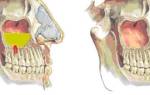

- Гайморит. Самая частая разновидность болезни поражает верхнечелюстные пазухи. Обычно диагностируется такой тип патологии у молодых людей до 20 лет. Пациенты этой возрастной категории и составляют основную группу риска по развитию в гайморовых синусах патологического воспалительного процесса грибковой природы.

Первоначальная терапия ГС основывается на полном удалении грибкового муцина (гелеобразного патологического секрета). Данная цель достигается исключительно оперативным путём. Хирургическое лечение грибкового синусита может проводиться при помощи операций различных типов – по способу Денкера (вскрытие воздухоносной полости через рот), классической гайморотомии и малоинвазивного эндоскопического вмешательства. Способ оперативного воздействия подбирается в зависимости от характера и течения патологического состояния.